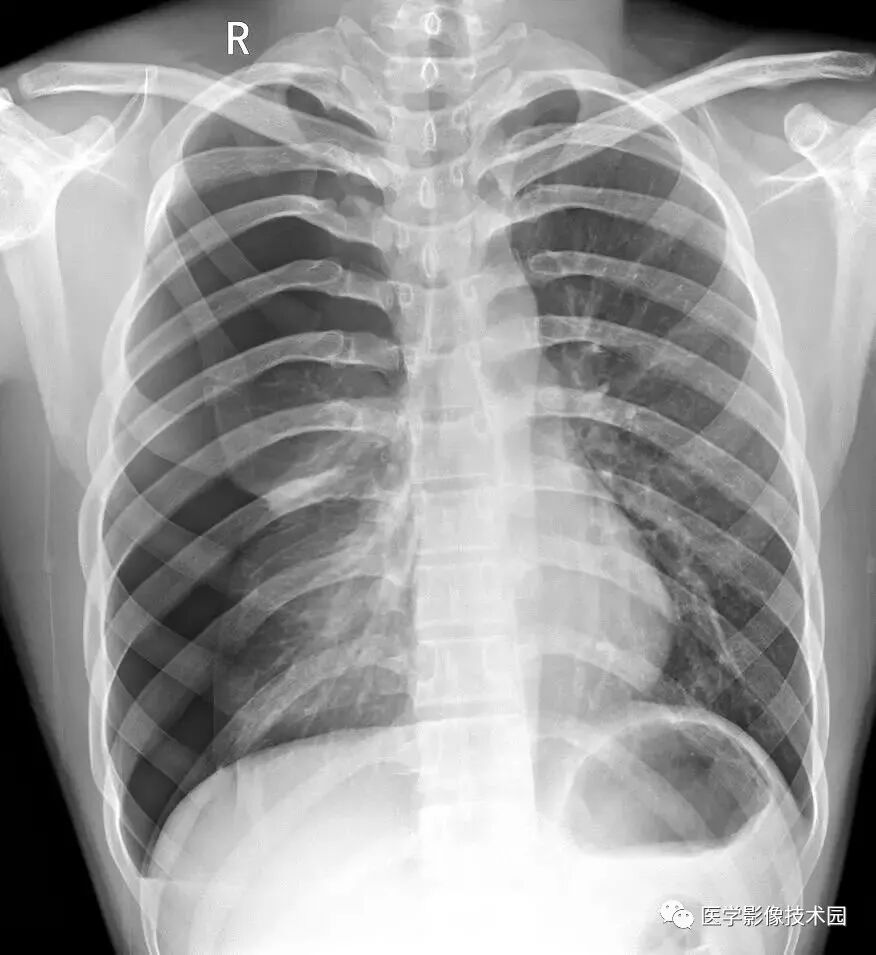

X线成像的基本原理

X线之所以能使人体组织在荧屏上或胶片上形成影像,一方面是基于X线的穿透性、荧光效应和感光效应;另一方面是基于人体组织之间有密度和厚度的差别。当X线透过人体不同组织结构时,被吸收的程度不同,所以到达荧屏或胶片上的X线量即有差异。这样,在荧屏或X线片上就形成明暗或黑白对比不同的影像。